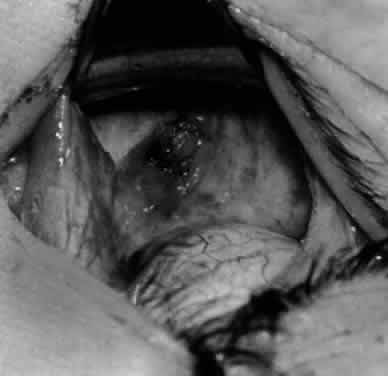

Fig. 14. The inferior temporal vortex vein, 8 mm posterior to the temporal insertion of the inferior rectus muscle, is held on a Green muscle hook.

Fig. 15. The placement of sutures within the sclera for a recession procedure of 10 mm. The anterior suture is placed 3 mm temporal and 2 mm posterior to the lateral insertion of the inferior rectus muscle, and the posterior suture is placed 3 mm further posteriorly.

Fig. 16. Two sutures straddle the inferior temporal vortex vein insertion for a 14-mm recession procedure.